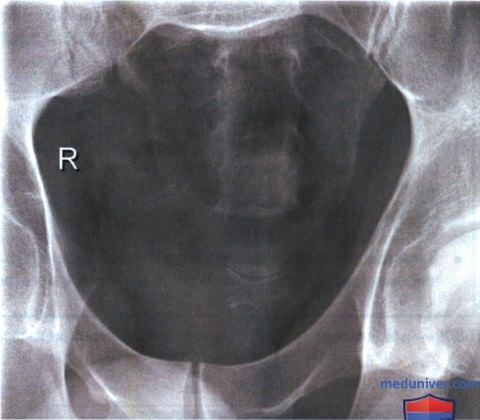

Рентгеновские снимки крестцово-копчикового отдела позвоночника